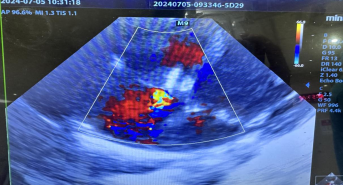

一小时后,亮亮的手术顺利完成,安全返回病房。紧接着,嘉嘉也被送进了手术室。手术十分顺利,仅历时半小时有余,嘉嘉便安全病房。术后两位患儿复查心脏彩超显示封堵器位置、形态正常,未见残余分流,均达到了预期效果。

嘉嘉术中彩超